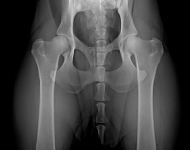

MVDr. Meloun: Lumbosakrální přechodový obratel